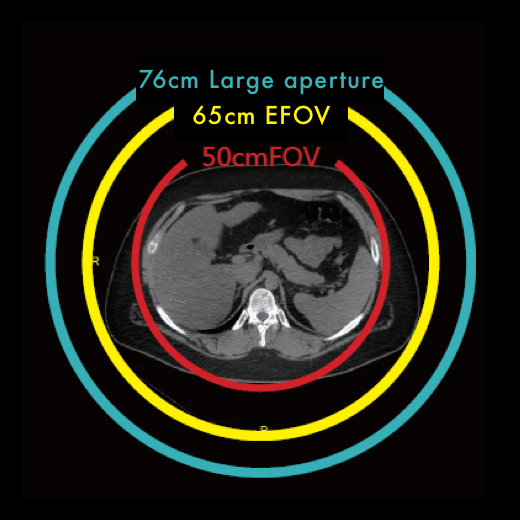

- Апература 76 см и увеличенное пространство сканирования позволяют расширить сферу применения оборудования.

Формирование скана и объемного изображения производится на цифровой матрице, которая состоит 1024 х 1024 элементов. Большое количество пикселей способствует формированию более контрастного, четкого и детального изображения всех анатомических областей с большим полем обзора.

- Максимальное поле обзора (max FOV): 50 см

- Максимальное поле обзора (max FOV): 65 см